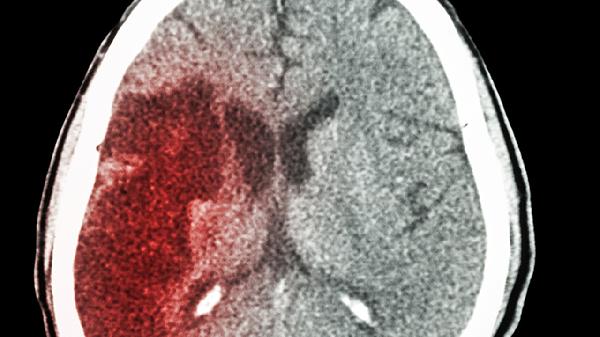

脑供血不足可通过调整生活方式、药物治疗、手术治疗等方式改善。脑供血不足可能与动脉粥样硬化、颈椎病、高血压等因素有关,通常表现为头晕、头痛、视物模糊等症状。